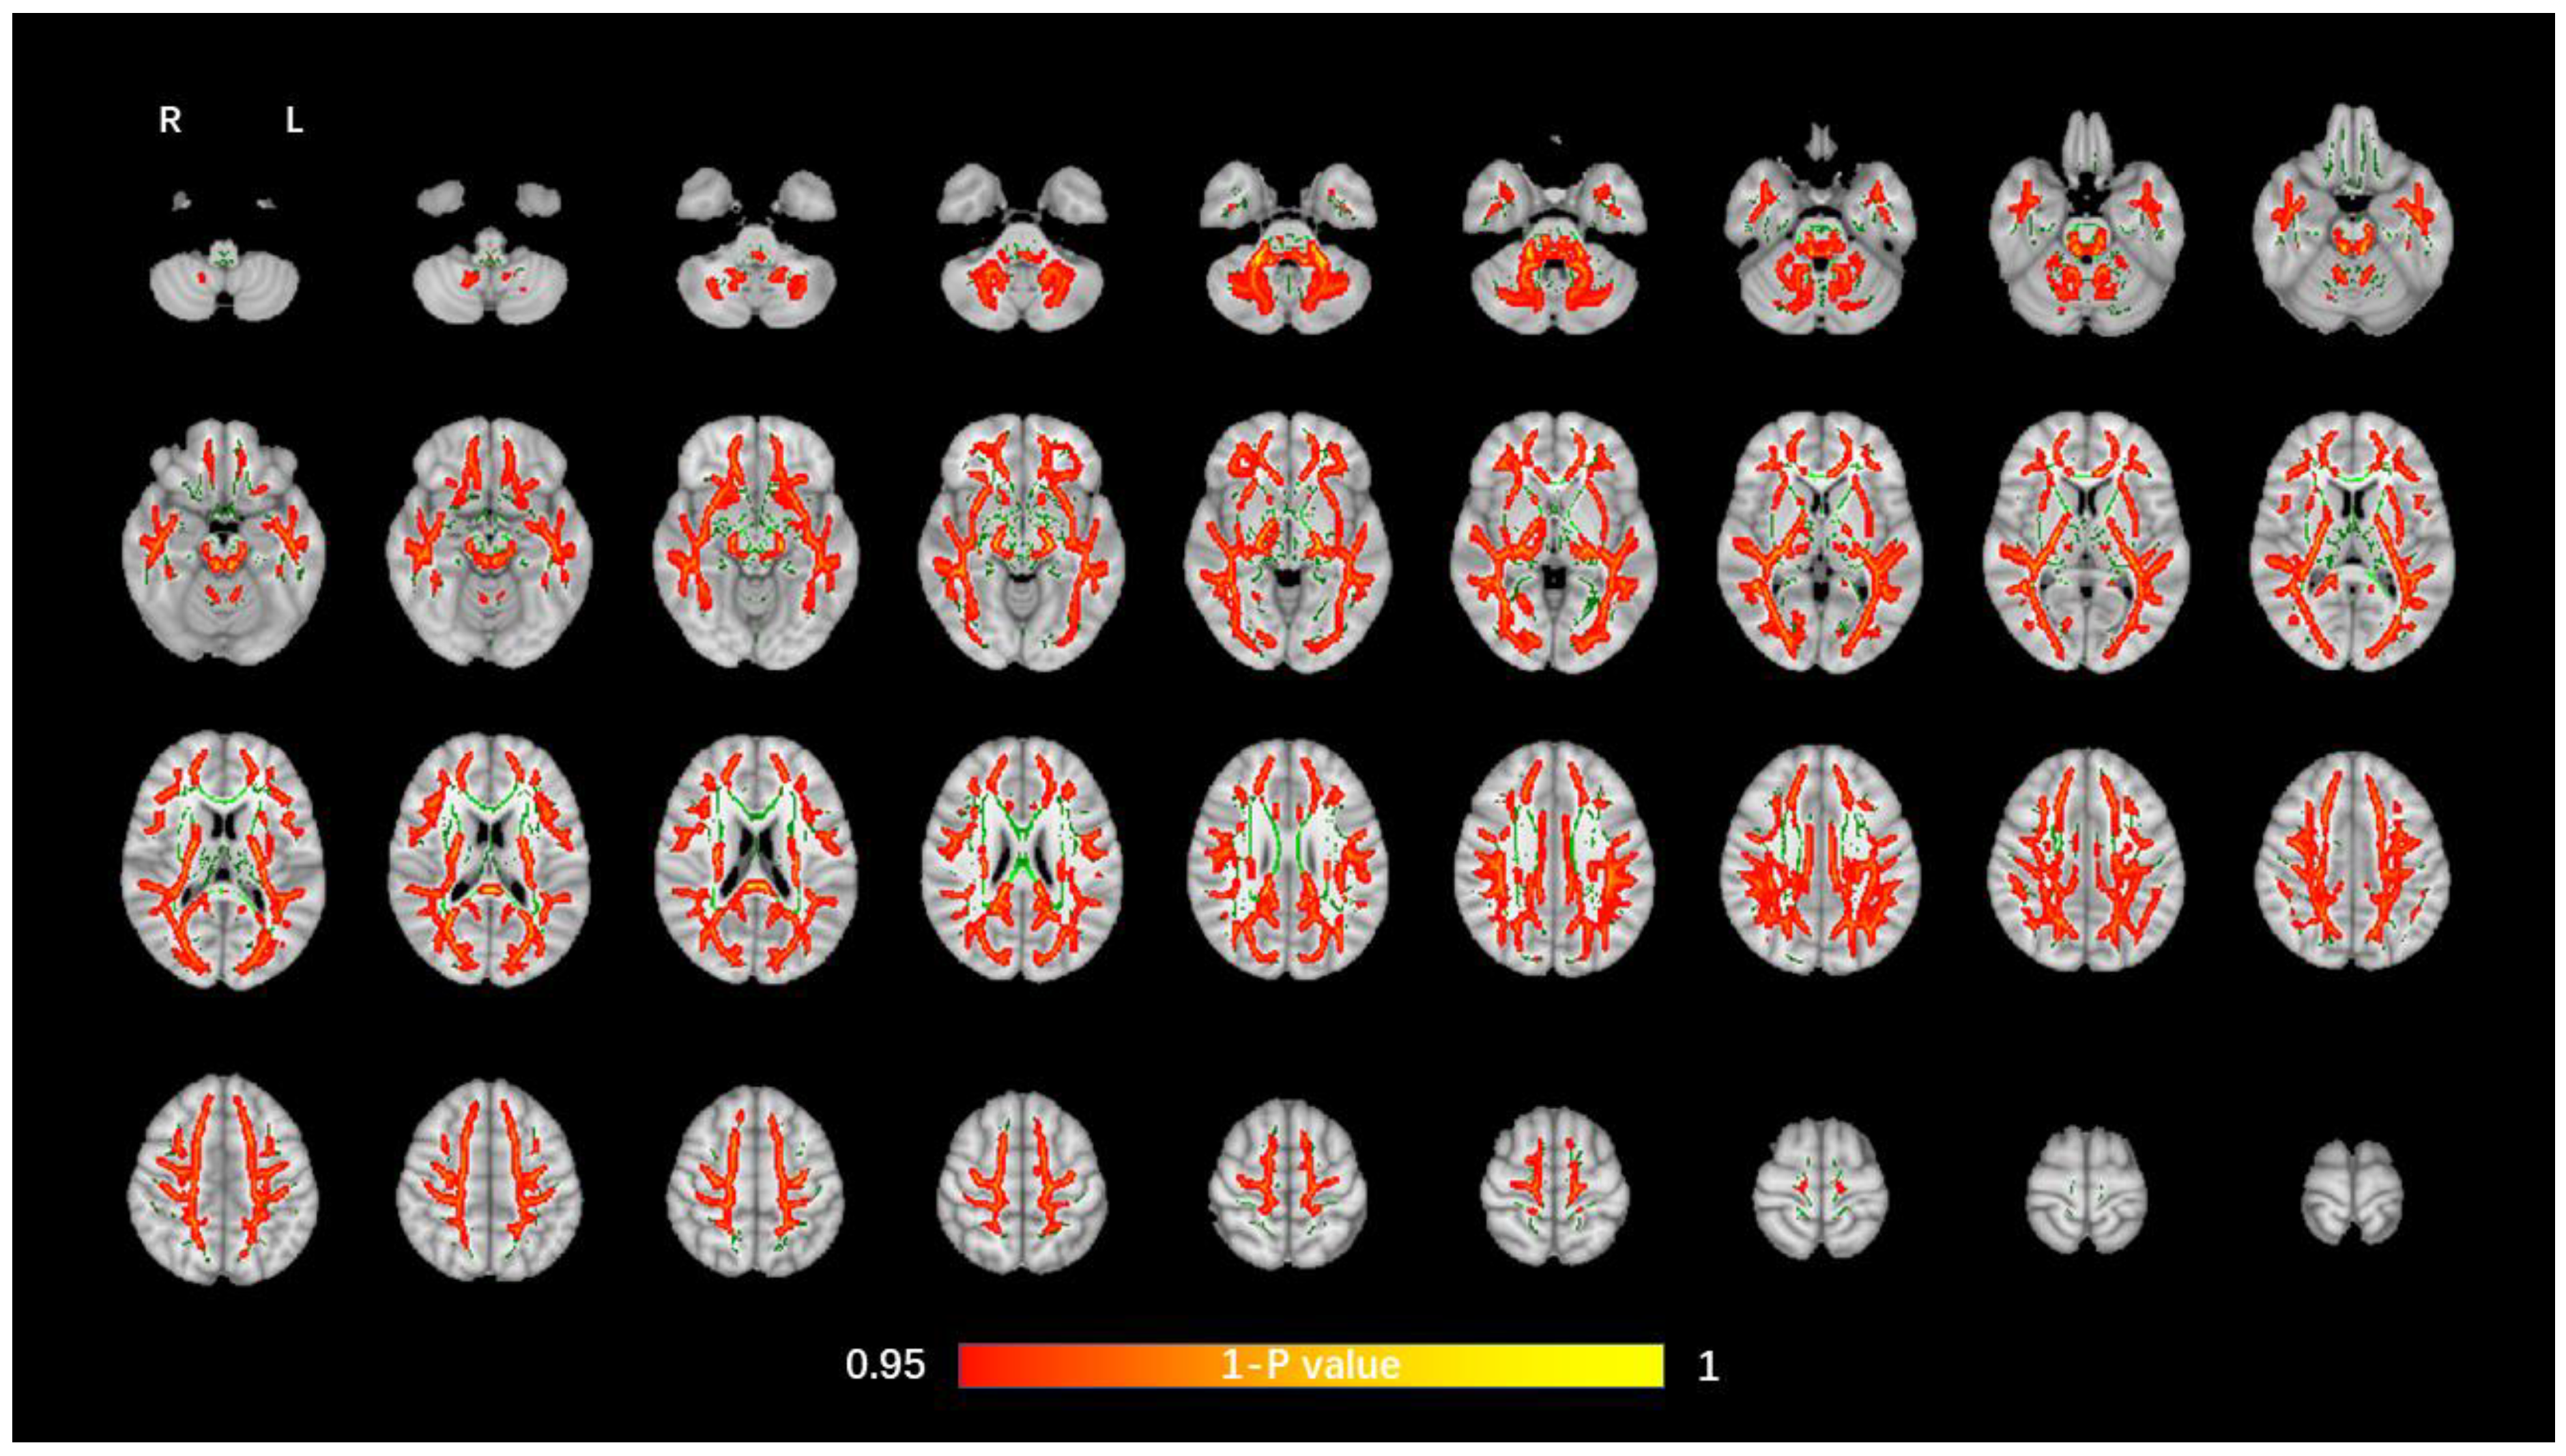

3.2. TBSS Analysis of DTI Data